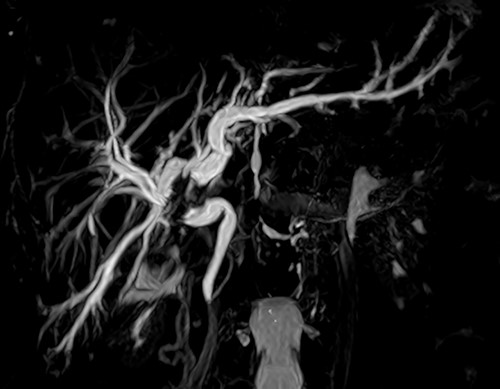

Screening for staging was performed, with ultrasound of the abdomen showing a suspicious neoplasia at the common hepatic duct. Cholangioresonance findings were suggestive of cholangiocarcinoma (Fig. 1). Computed tomography (CT) demonstrated a solid and irregular nodule (Fig. 2).

Cholangioresonance showing biliary tract dilatation due to intraductal lesion of the biliary tract, involving the confluence and the right hepatic duct (Bismuth IIIA).